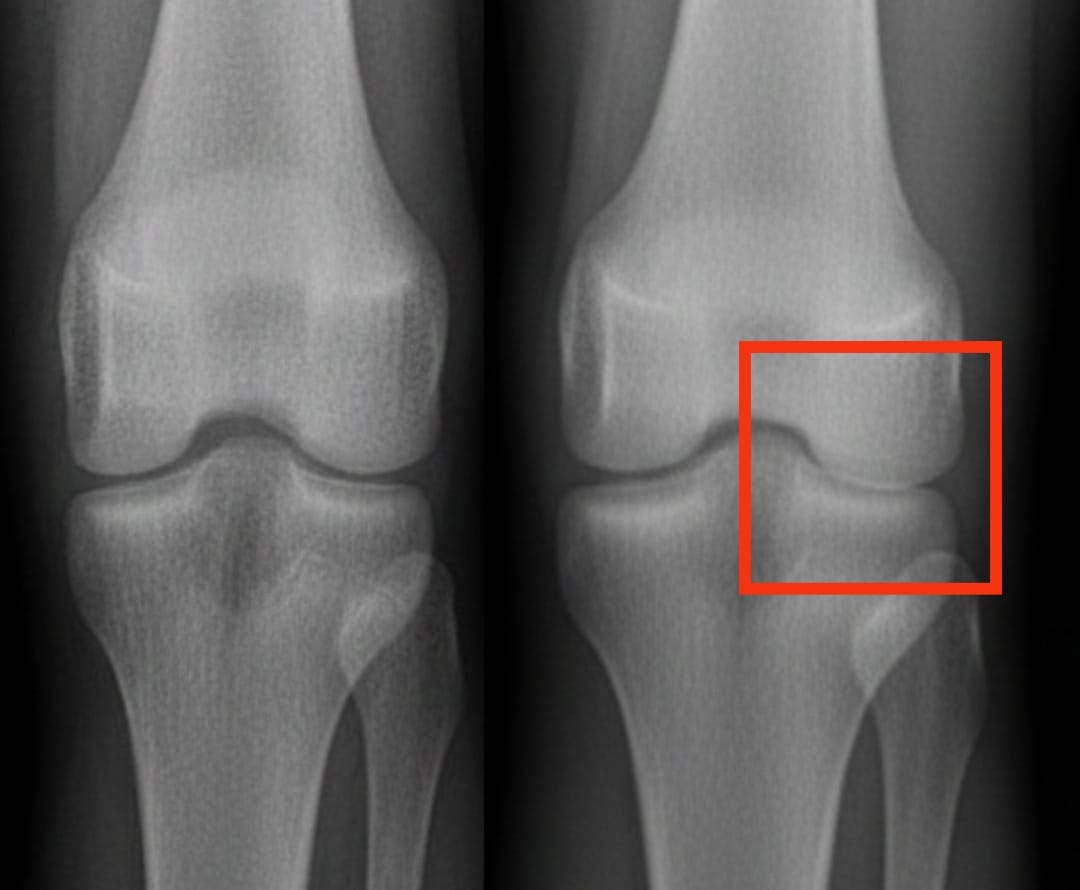

血小板豊富な血漿は、膝関節症に対する他の注射治療よりも効果的ですか?

膝関節症は世界中で数億人に影響を与えています。これは、軟骨の進行性摩耗によって痛みや動きの困難を引き起こします。提案されている解決策の中でも、血小板豊富な血漿の注射が注目を集めています。この治療法は、患者自身の血液を用い、血小板を濃縮させることで組織の修復を促進し、炎症を軽減します。

最近の分析では、血小板豊富な血漿の有効性を、ヒアルロン酸、コルチコステロイド、および生理食塩水プラセボといった他の一般的な注射治療と比較しました。その結果、血小板豊富な血漿は6か月後には痛みと可動性を著しく改善し、その効果は1年間持続することがわかりました。これらの改善は、ヒアルロン酸やコルチコステロイドによるものよりも顕著であり、プラセボを大きく上回ります。